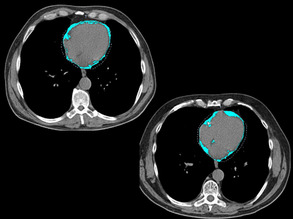

Seeing Double